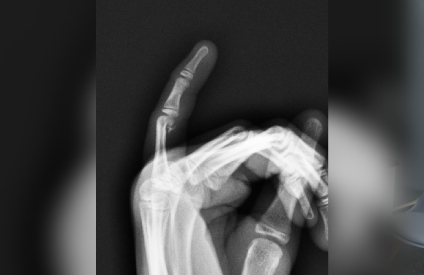

Our state-of-the-art digital X-ray facility provides immediate, high-quality imaging services right at our clinic. This advanced technology allows our specialists to quickly assess your condition and begin appropriate treatment without delay.

Digital X-rays offer superior image quality compared to traditional X-rays, with lower radiation exposure and instant availability for review, enabling faster and more accurate diagnoses.

Our digital X-ray services are essential for diagnosing various orthopaedic conditions, monitoring healing progress, and planning treatments. We use this technology for fracture detection, joint assessments, and pre-operative planning, ensuring precise and effective care for our patients.